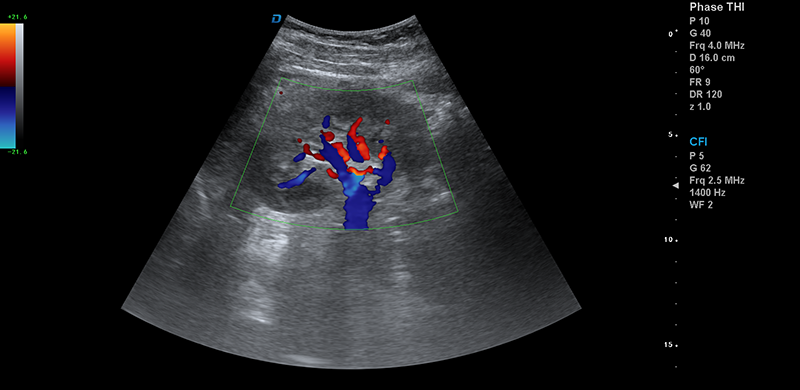

●能量多普勒成像(PDI)

●方向性能量多普勒(DPDI)

●B/C/D三實時成像

組織多普勒成像(TDI):TDI成像技術的應用在心臟檢查方面大大提高了臨床醫生的診斷信心,通過心肌功能的運動捕捉,可對血管壁和心臟組織的運動速率進行精確的測定。